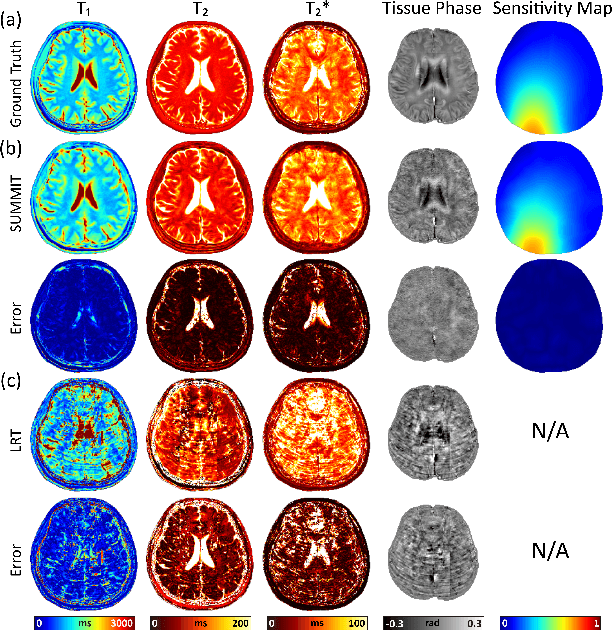

Abstract:Quantitative magnetic resonance imaging (qMRI) offers tissue-specific physical parameters with significant potential for neuroscience research and clinical practice. However, lengthy scan times for 3D multiparametric qMRI acquisition limit its clinical utility. Here, we propose SUMMIT, an innovative imaging methodology that includes data acquisition and an unsupervised reconstruction for simultaneous multiparametric qMRI. SUMMIT first encodes multiple important quantitative properties into highly undersampled k-space. It further leverages implicit neural representation incorporated with a dedicated physics model to reconstruct the desired multiparametric maps without needing external training datasets. SUMMIT delivers co-registered T1, T2, T2*, and quantitative susceptibility mapping. Extensive simulations and phantom imaging demonstrate SUMMIT's high accuracy. Additionally, the proposed unsupervised approach for qMRI reconstruction also introduces a novel zero-shot learning paradigm for multiparametric imaging applicable to various medical imaging modalities.